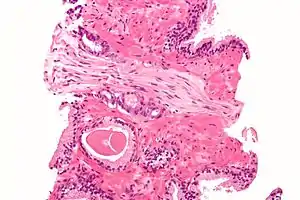

Micrograph demonstrating perineural invasion. HPS stain.